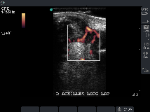

Achilles Tendon: Power Doppler correlation depicting acute nature of swelling.